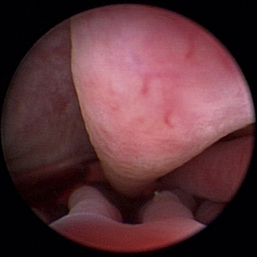

Normal turbinates have a smooth, pink-to-white surface and a spatial alignment that provides channels for the passage of air. The color varies and appears tan in the caudal nasal cavity. Turbinates come in different shapes and sizes, but the surface should be smooth. Ethmoid turbinates in the caudal nasal cavity will have a characteristic stippled or corrugated appearance (Figures 19-13 through 19-16). Ulcerations or various proliferations of the mucosa are indicative of disease. These changes are typically diffuse and accompanied by a lot of mucus. Mucus can be thin to purulent. Copious amounts can be flushed out of the nasal cavity to allow better visibility. The specific disease is determined by biopsy. After full examination of the nasal cavity, run the scope along the floor of the nasal sinus to the level of the choanae. Keeping the scope pointed in a ventral medial direction prevents inadvertent trauma or penetration of the cribriform plate. The index finger of the free hand can be used to follow the scope as it moves caudally over the hard palate; the surgeon can then palpate the scope through the soft palate when it moves into the nasopharynx. Some force is needed to complete this procedure and may result in increased bleeding.

image

Figure 19-14 Normal canine meatus division.